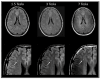

Mitochondria play a crucial role in human biology, affecting cellular processes at the smallest spatial scale as well as those involved in the functionality of the whole system. Imaging is the most important research tool for studying the fundamental role of mitochondria across these diverse spatial scales. A wide array of available imaging techniques have enabled us to visualize mitochondrial structure and behavior, as well as their effect on cells and tissues in a range from micrometers to centimeters. Each of the various imaging techniques that are available offers unique advantages tailored to specific research needs. Selecting an appropriate technique suitable for the scale and application of interest is therefore crucial, but can be challenging due to the large range of possibilities. The aim of this review is two-fold. First, we provide an overview of the available imaging techniques and discuss their strengths and limitations for applications across the sub-mitochondrial, cellular, tissue and organ levels for the imaging of mitochondria. Second, we identify opportunities for novel applications and advancement in the field. We emphasize the importance of integration across scales in mitochondrial imaging studies, particularly to bridge the gap between microscopic and non-invasive techniques. While integrating these diverse scales is challenging, primarily because such multi-scale approaches require expertise that spans different imaging modalities, we argue that integration has the potential to provide groundbreaking insights into mitochondrial biology. By providing a comprehensive overview of imaging techniques, this review paves the way for multi-scale imaging initiatives in mitochondrial research.